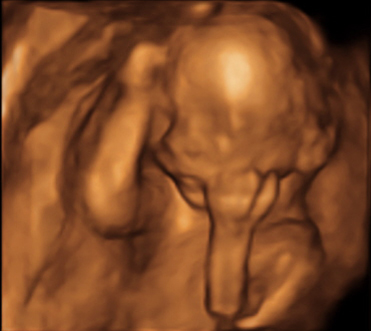

Baba-Nuus: Ons was Vrydag vir ons 19 weke 'scan' om te kyk dat alles reg is en daar is. Alles is 100%. Ons het ook 'n paar mooi fototjies gekry. (Ek het hierdie dalk al vroër die week aan verskeie mense 'gespam' sonder 'n beskrywing. Jammer, skryf dit maar af aan 'n trotse pa-to-be.)

3D Scan (Dis nie 'n slurpie nie, dis sy arm. Sy kop is effens na die linkerkant van die foto gedraai. Kobus reken hy lyk soos die denker.) |